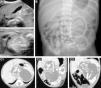

(A) Abdominal ultrasound. (B) Plain radiograph of the abdomen; the oval shape marks the location of the longitudinal bone structures. (C) Abdominal CT scan: well-delineated mass containing calcified structures that correspond to the long bones and vertebrae of the FIF; (C1) axial plane, (C2) sagittal plane; (C3) oblique plane.

We present the case of a full-term male newborn with an abdominal mass detected by ultrasound at 25 weeks of gestation. The physical examination was unremarkable. He had elevated levels of ferritin, lactate dehydrogenase (LDH), ¿-human chorionic gonadotropin (¿-HCG) and alkaline phosphatase (AP), while test results were normal for the complete blood count, renal function, ¿-foetoprotein and carcinoembryonic antigen. Urine catecholamine values were normal. Abdominal ultrasonography revealed a well-delineated retroperitoneal lobulated solid mass surrounded by fluid that contained linear calcifications resembling bone structures (Fig. 1A). Abdominal radiography showed mature bone structures resembling long bones in the left flank (Fig. 1B). Computed tomography (CT) of the abdomen confirmed these findings and provided detailed information on the relationship of the mass with important vascular and visceral structures (Fig. 1C). The surgical exploration, performed at 5 days of life, revealed an encapsulated mass. Sectioning of this mass yielded a clear fluid and a foetiform mass with four limbs and a rudimentary umbilical cord measuring 8mm that extended into a membrane-like tissue that corresponded to the amnion (Fig. 2). The anatomopathological study described a foetiform structure covered in skin with arrhinia, anophthalmia, acrania, and rachischisis. A tongue, tooth buds, trachea, oesophagus, intestine, bladder, pancreatic and testicular tissue, adrenal gland, spinal cord with bone marrow, and pelvis were identified. Malignancy was ruled out. At 48h post-surgery, the patient had abdominal distension and elevated serum inflammatory markers, and radiography of the abdomen showed pneumatosis intestinalis. Necrotising enterocolitis was suspected and antibiotic therapy initiated. The surgical reintervention confirmed ischaemic necrosis of the terminal ileum extending to the ascending colon, secondary to the ligation of a branch of the superior mesenteric artery. Right hemicolectomy, distal ileostomy, and transverse colostomy were performed. The postoperative period was uneventful, and the levels of ferritin, LDH, ¿-HCG and AP normalised. Bowel reconstruction was performed 3 months later by end-to-end anastomosis, with no complications. The clinical outcome was excellent at 12 months, and the patient showed appropriate height and weight gains.